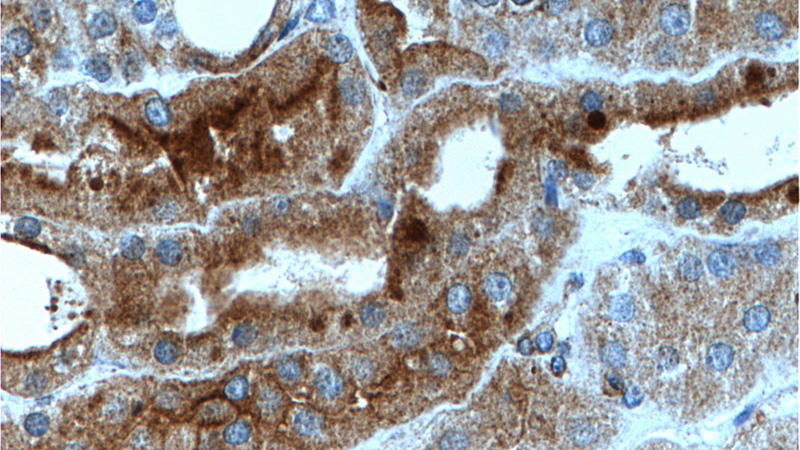

Immunohistochemistry of paraffin-embedded human kidney tissue slide using Catalog No:113308(NOTCH1 Antibody) at dilution of 1:200 (under 40x lens).